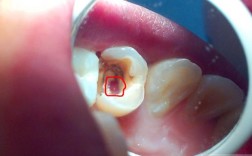

🦷 一、 龋齿(蛀牙/虫牙) - 最常见的牙齿问题

这是牙齿硬组织(牙釉质、牙本质)被细菌分解破坏的过程。

充填治疗(补牙):

- 适用情况: 龋坏仅限于牙釉质或较浅的牙本质层,未伤及牙髓(牙神经)。

- 方法: 牙医会去除腐坏的组织,然后用充填材料(如复合树脂、玻璃离子水门汀、银汞合金等)恢复牙齿的外形和功能,复合树脂美观,应用最广。

- 优点: 简单、快速、能有效阻止龋坏进展、恢复咀嚼功能。